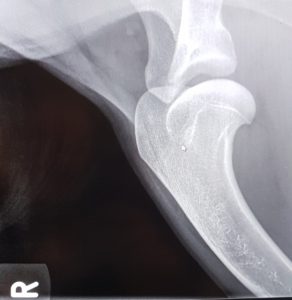

Endnu 2 hunde er blevet bedømt af DKK og fundet HD, AD og OCD frie, vi er så glade og stolte!